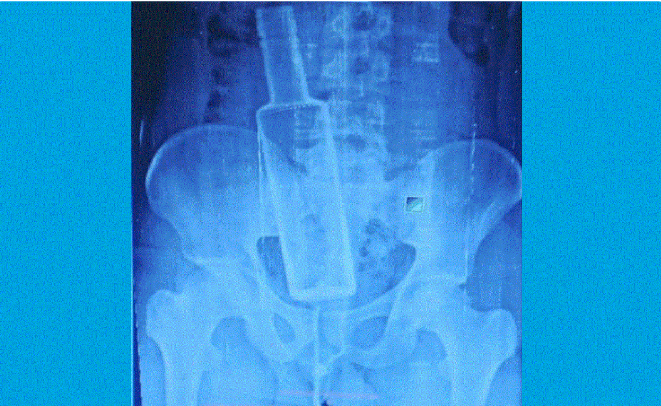

रौतहटको गुजरा नगरपालिका–९ का २६ वर्षीय नुर्साद मन्सुरीको पेटबाट सल्यक्रिया गरी बोतल निकालिएको छ । पेट दुखेपछि उपचारका लागि चन्द्रपुर अस्पताल लगिएका नुर्सादको एक्सरे गर्दा पेटमा सिसाको बोतल देखिएपछि थप उपचारका लागि उनलाई चितवनको पुरानो मेडिकल कलेज लगिएको थियो ।

चितवनस्थित पुरानो मेडिकल कलेजका डा. नारायण बेलबासे र एनेसथेसिया डा. राजेश यादवसहितको टोलीले पेटको शल्यक्रिया गरेर सिसाको बोतल निकालेको थियो । शल्यक्रियाको ४ घण्टापछि सोमबार साँझ मात्र नुर्सादको होस आएको डा. बेलबासेले बताए ।